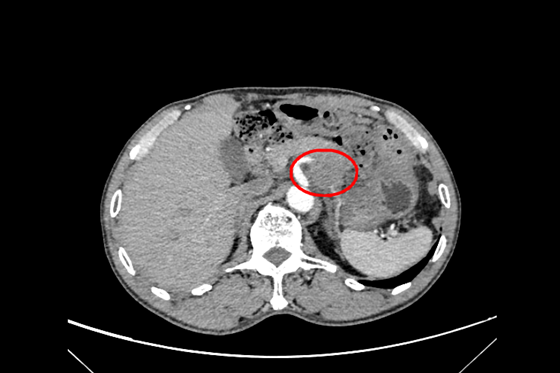

图示肿物与血管关系

廖国庆教授接诊病人后,尽快安排患者完善术前检查。增强CT等影像显示:胃小弯处肿瘤,大小约5×4cm,考虑胃恶性肿瘤,肿瘤与胰体尾部及脾动脉关系密切,不排除胰腺肿瘤可能。廖国庆教授表示:单纯行近端胃切除术可能无法完整切除肿瘤,术中可能需行联合脏器,即:近端胃+胰腺体尾部+脾脏切除术,才能将完整切除肿瘤,达到根治性切除。但手术难度大,创伤大,肿瘤包绕腹腔干,因腹腔干由腹主动脉发出,并分出胃左动脉,脾动脉,肝总动脉三支重要血管及其分支血管为胃、脾脏、肝脏、胰腺及十二指肠等重要器官供血,此处结构复杂,重要血管交错,稍有不慎极易出现大出血的情况对医患双方都是巨大挑战。经团队讨论后,结合患者一般情况,最终决定为患者实施手术治疗。术中探查也证实了术前判断,肿物与胃、胰腺及脾动脉密不可分,最终为患者实施:近端胃切除术+胰体尾部切除术+脾切除术+淋巴结清扫术。同时,采用“双通道法”为患者进行消化道重建,减少反流性食管炎及因维生素B12缺乏导致的巨幼红细胞贫血发生的可能性。